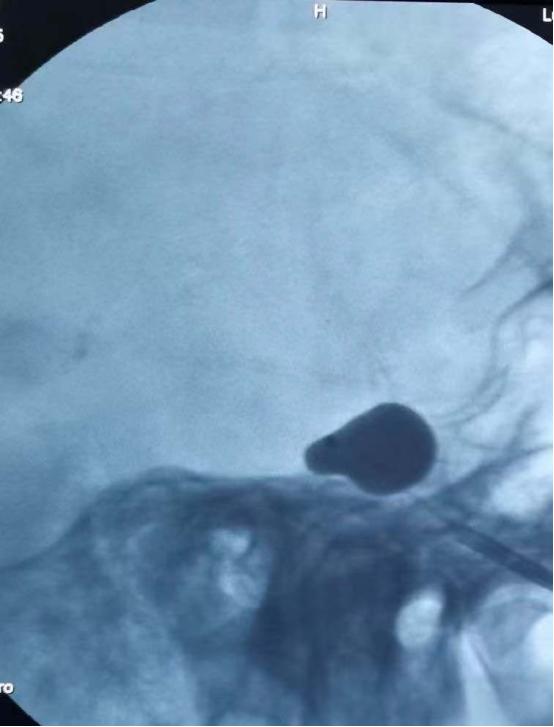

8月30日,由华安脑科医院院长傅先明教授、副院长杨先清教授、谢英贺副主任等神经外科组成的专家团队经过讨论,在征得家属同意后,决定为刘奶奶进行DSA引导经皮穿刺三叉神经半月节球囊压迫术。

该手术是经面部皮肤穿刺到达三叉神经半月节的部位,通过球囊导管适度压迫,达到控制疼痛的效果。整个创口仅一针眼大小,在我院引进的美国GE双板DSA的影像设备精准定位下完成,该设备一次注射造影剂同时显影正、侧位血管影像,可清晰显示血管造影。